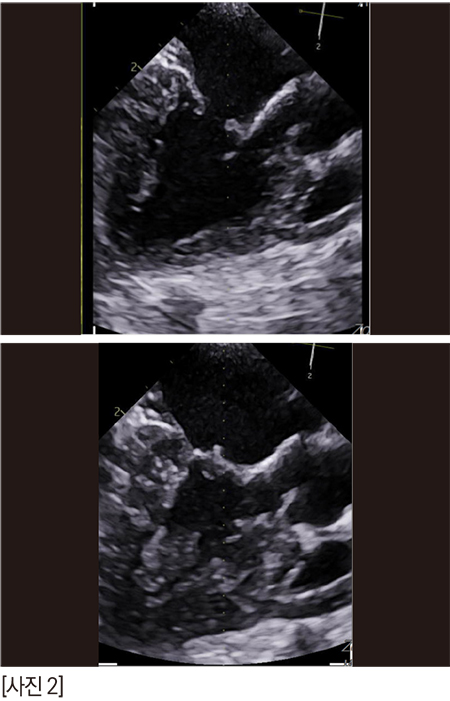

짱아의 방사선은 이렇다. 오랫동안 MMVD B2 로 유지되고 있다.

콩팥에는 결석이 있고, 복부초음파에서 콩팥은 점점 나이가 들어가고 있는 것은 확실하다.